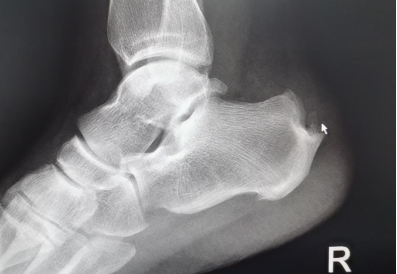

“經(jīng)X光、磁共振等詳細(xì)檢查,提示患者雙側(cè)跟骨結(jié)節(jié)增生、跟腱有變性,雙側(cè)跟骨結(jié)節(jié)區(qū)域及跟腱止點(diǎn)表現(xiàn):組織充血、水腫,結(jié)合病情及查體,考慮跟骨骨性突起畸形,經(jīng)診斷,為Haglund綜合癥(止點(diǎn)性跟腱炎、跟骨后上突增生與跟腱滑囊炎的統(tǒng)稱)?!崩畋蛑魅伪硎荆摬“Y主要表現(xiàn)為跟腱止點(diǎn)部位疼痛不適,運(yùn)動時疼痛加劇;或者清晨起床后出現(xiàn)疼痛,漸進(jìn)性病程發(fā)展,后期疼痛加重,影響生活質(zhì)量。

考慮患者術(shù)后行動問題,8月18日,在李彬主任的帶領(lǐng)下,手術(shù)團(tuán)隊首先為其治療疼痛更甚的右腳。術(shù)中,僅開了兩個很?。ㄖ睆?毫米左右)的口子,在關(guān)節(jié)鏡下磨除右側(cè)跟骨后增生骨質(zhì),去除骨撞擊,清理炎性組織,手術(shù)順利完成。